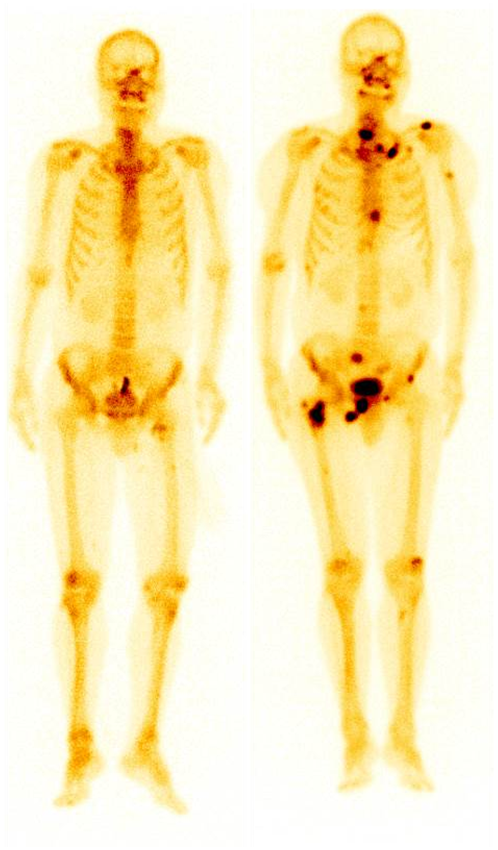

例如上圖,左圖好比常規CT、MR等解剖影像,細節清晰,但不能發現形態正常和輕度異常的病變;右圖類似功能影像,直接將病變點亮,一目了然。

肺腺癌患者,左圖為2018年12月ECT,未見明顯異常;期間未復查;2023年5月骨痛來診,ECT顯示全身多發骨轉移(右圖)。